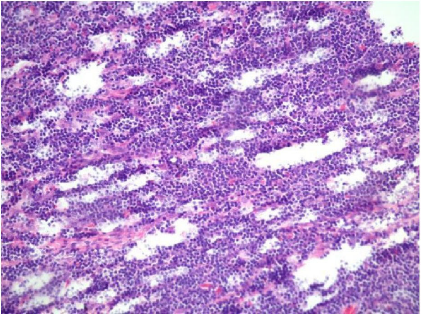

Observe a imagem abaixo:

No estudo de tecidos, é importante lembrar que o resultado final pode ser distorcido em qualquer das etapas. Com base nessa imagem, pode-se dizer que o artefato ocorreu no seguinte momento: